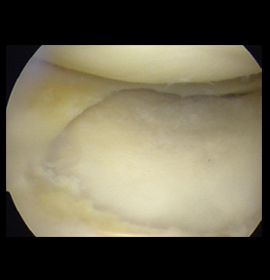

La artroscopia es una técnica quirúrgica de mínima invasión, la cual consiste en la introducción, de una camara (artroscopio) en una articulación mediante una pequeña incisión en la cual nos permite realizar una evaluación completa, un diagnóstico y al mismo tiempo realizar un tratamiento en las articulaciones. ofreciendo mejores resultados, como por ejemplo en lesiones de manguito rotador, lesiones meniscales o ligamentarias de rodilla u otras articulaciones como tobillo, brindando mayor rapidez de recuperación y reduciendo las probabilidades de complicaciones en comparación con las técnicas abiertas.

Una rotura del menisco es una de las lesiones de rodilla más comunes. Cualquier actividad que haga que tuerzas o gires la rodilla con fuerza, especialmente al poner todo tu peso sobre ella, puede llevar a que ocurra una rotura del menisco.